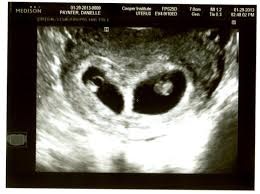

Sindromul geamanului care dispare a fost definit pentru prima data in 1945. Sindromul gemanului care dispare este un sindrom in care unul dintre gemeni (doi sau mai multi)...